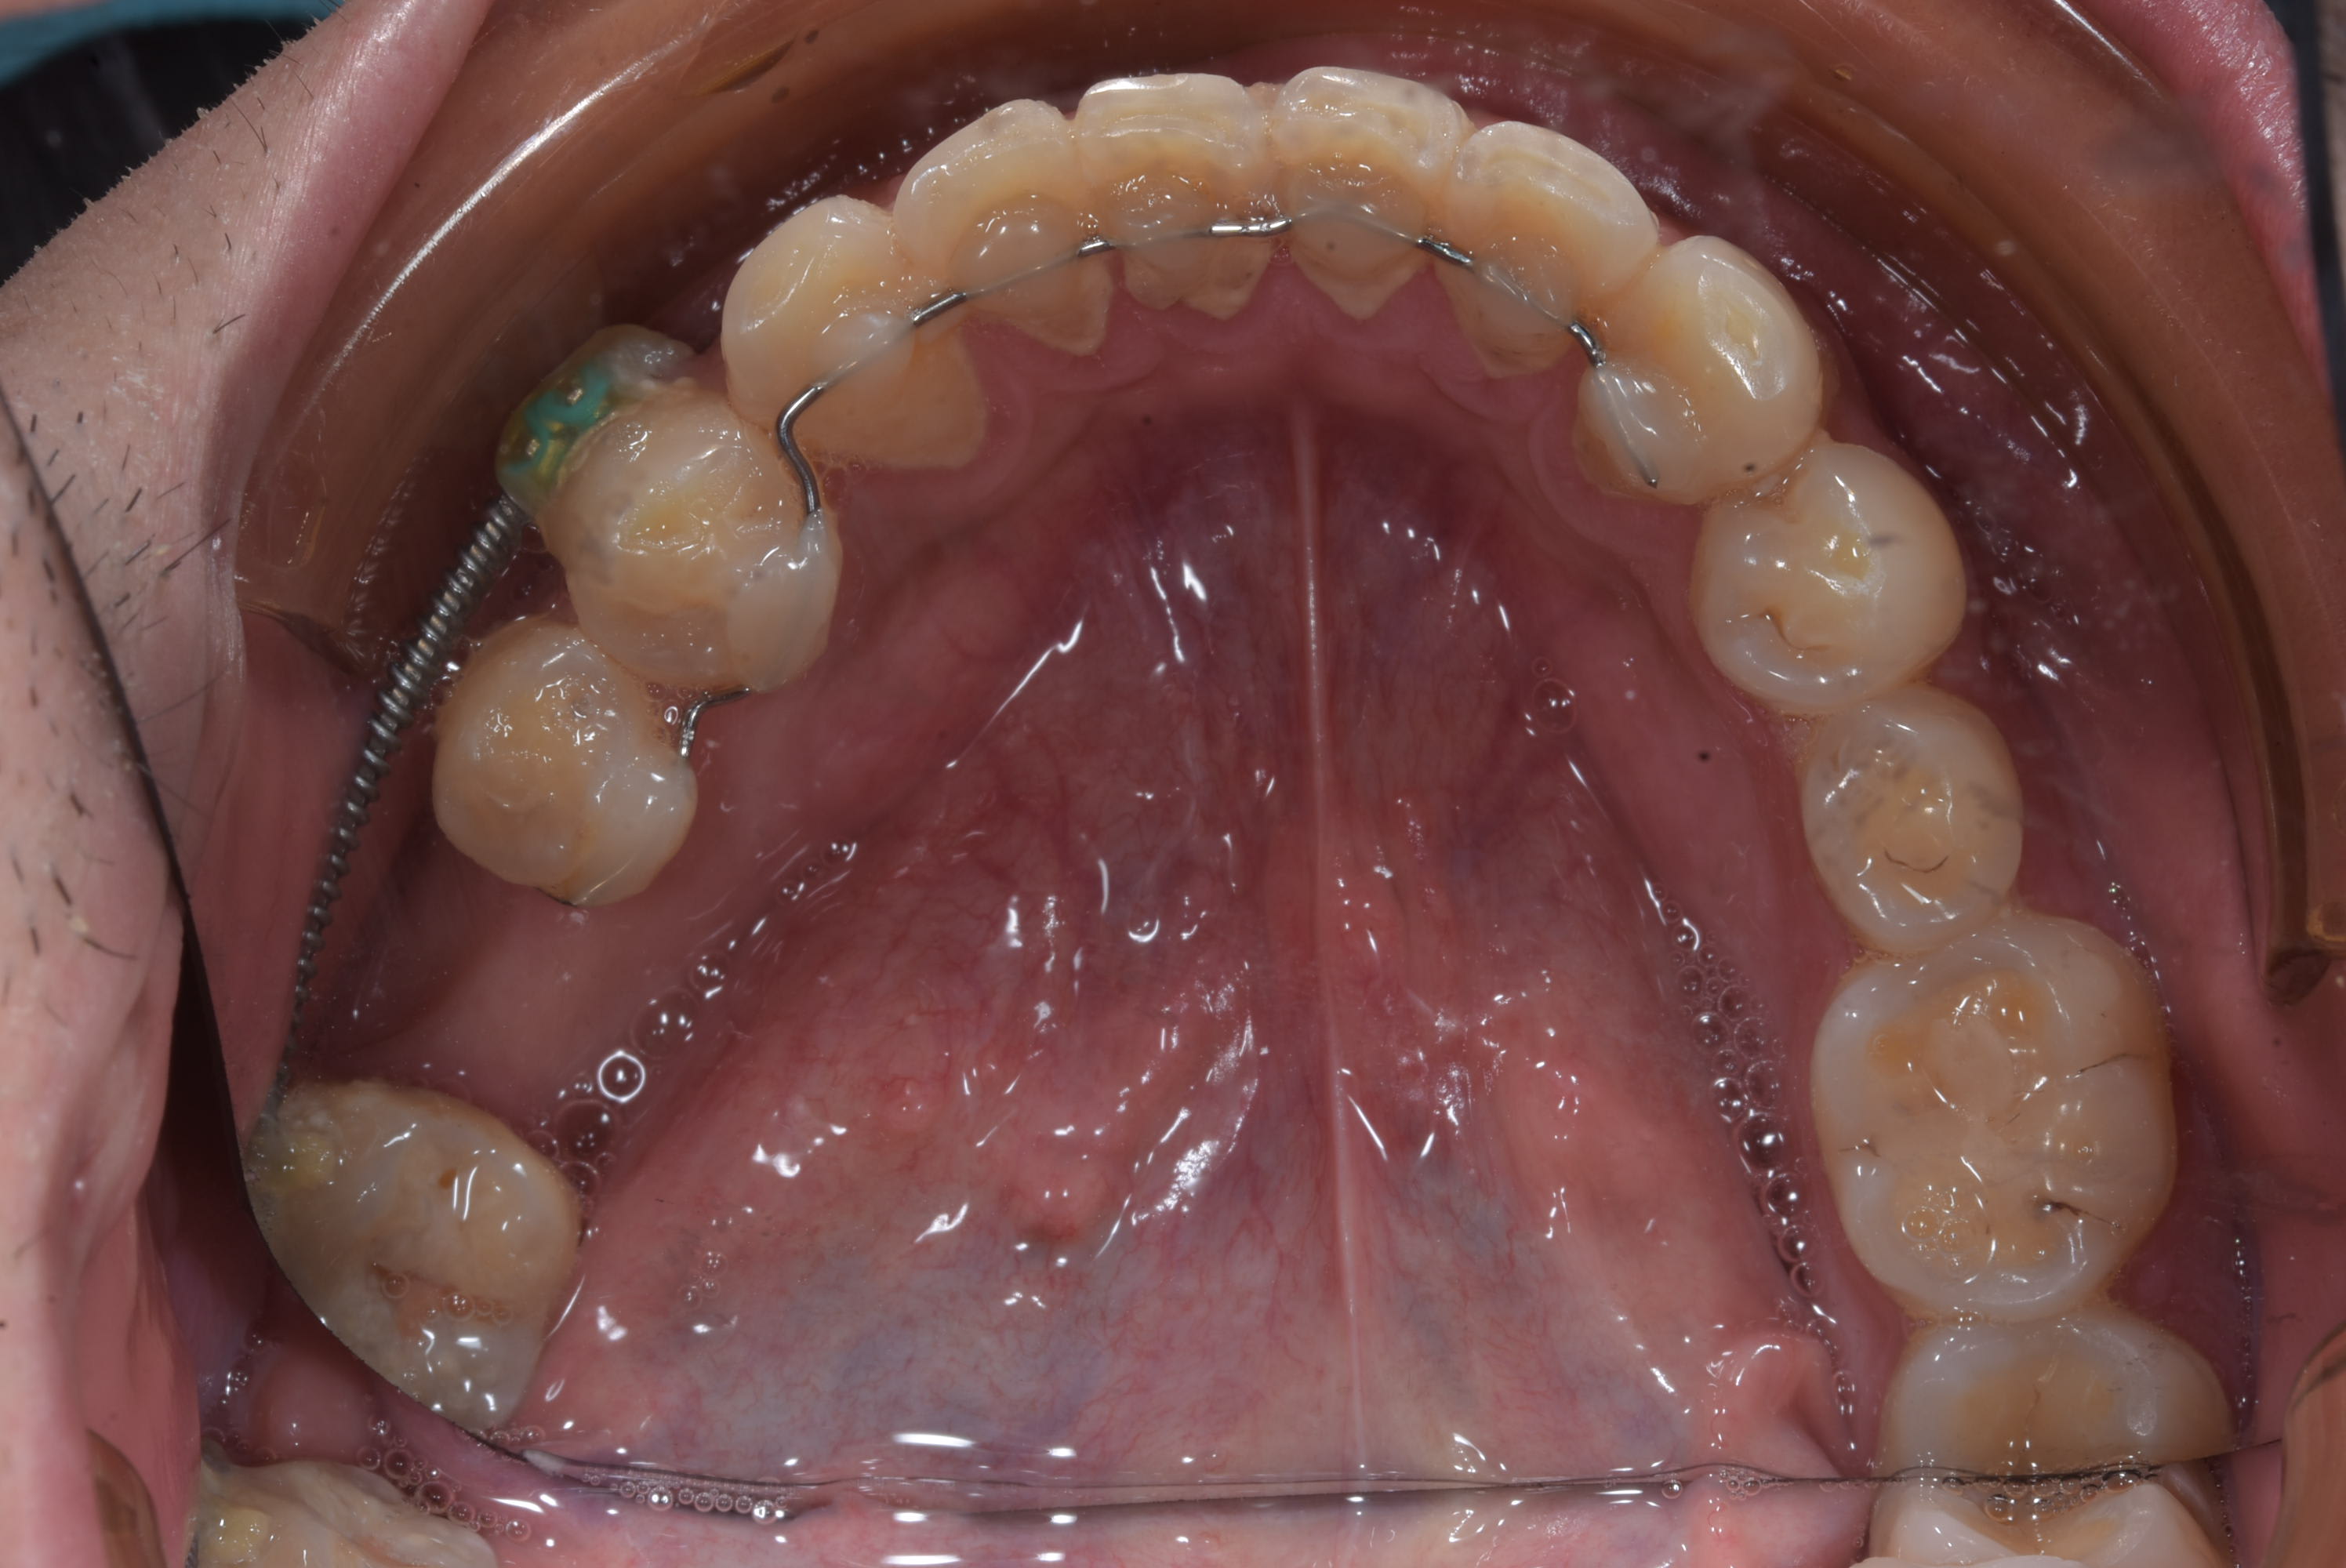

Et l'espace est suffisamment ouvert pour implanter. Je vous posterais les radios ce soir.

L'implant sera poser dans la semaine et je baguerait trois mois plus tard.

Pour le patient ça veut dire 6 ou 7 mois ou il évite d'être appareillé pour rien, pour moi c'est 6 ou 7 mois ou le temps fauteuil est quasi nulle.

Bref une solution gagnant gagnant.

Patient vue aujourd'hui. Quatre mois de traitement .

Patient qui ne vient pas au rendez vous et se plaint de tout, bref je doute que ça se soit bien passer en baguant toutes les dents :-)